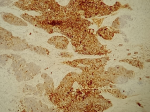

Intervention thérapeutique: devant ce tableau clinique, une intervention chirurgicale par voie combinée a été faite. La voie endonasale a permis l'exérèse de la tumeur par fragmentation, en réalisant une ethmoïdectomie antérieure, postérieure et un accès au sinus frontal. Cependant, la tumeur envahit l'orbite et une voie externe pour un meilleur contrôle de la tumeur a permis la perméabilisation du canal frontal et l'exérèse complète de la tumeur intrafrontale. L'étude histologique de la pièce opératoire a révélé une prolifération carcinomateuse indifférenciée, faite de lobules et de massifs noyés dans un stroma fibreux avec foyer de nécrose (HE x 10) (Figure 4). Les cellules tumorales sont dotées de noyaux atypiques, sans signe de différenciation malpighienne ou glandulaire (HE x 40) (Figure 5). Elles expriment la CKAE1AE3 (Figure 6) et la CK7 (Figure 7). L'INI 1 est retenu. La CK5/6, P63 et la synaptophysine sont négatives.

Figure 6: cellules tumorales expriment la CKAE1AE3

Figure 7: cellules tumorales expriment la CK7